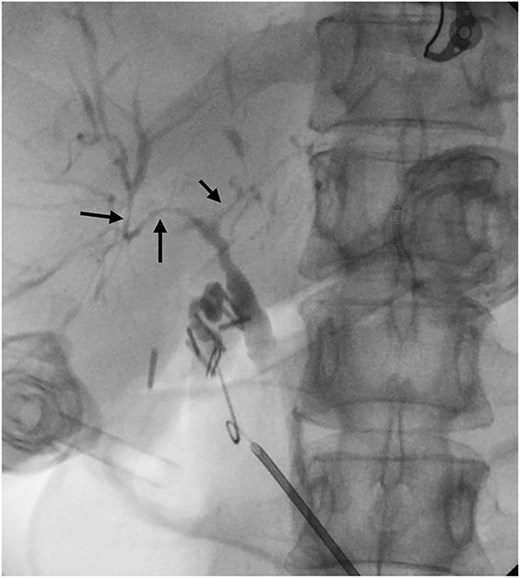

A 54-year-old female with a recent diagnosis of IBD complicated by PSC, presenting with right upper quadrant pain, underwent abdominal ultrasound, and magnetic resonance cholangiopancreatography (MRCP) as part of her PSC workup. Ultrasound demonstrated two 7 mm gallbladder polyps, with a normal gallbladder wall. MRCP demonstrated segmental intrahepatic duct dilatation in segments II and VIII in keeping with PSC (Fig. 1). Initial liver function tests and Ca 19.9 level showed only a mildly elevated GGT and ALP. Due to the recent diagnosis of IBD and small size of gallbladder polyps, observation with progress imaging at 12 months was undertaken. Repeat MRCP demonstrated a slight outpouching of the wall of the gallbladder with subtle enhancement of the lateral wall, with no concerning features for malignancy.

Magnetic resonance imaging liver/MRCP demonstrating subtle intrahepatic biliary dilatation (arrows), most pronounced in segment 8.